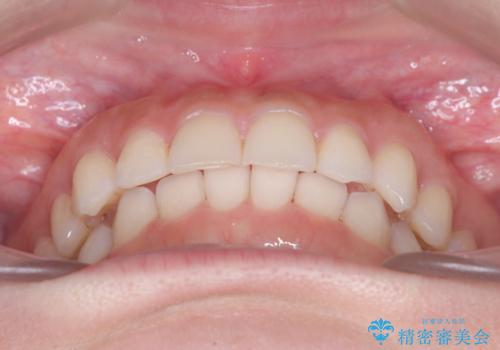

- 前歯のガタガタが気になるとのことでご相談いただきました。診察すると、歯列のスペースが不足し、前歯が重なっている状態でした。抜歯をせずに整えるため、歯と歯の間をわずかに削るIPR(歯列幅径削除)と、奥歯を後方へ動かす遠心移動を組み合わせてスペースを確保しながら並べる治療計画を立てました。

インビザラインを用いて歯を少しずつ移動させながら、IPRで微調整を行い、スペースを確保しました。また、奥歯を遠心移動させることで、前歯を自然な位置に並べることができました。治療後は、「ガタガタがなくなり、スムーズな歯並びになった」と患者様にもご満足いただきました。